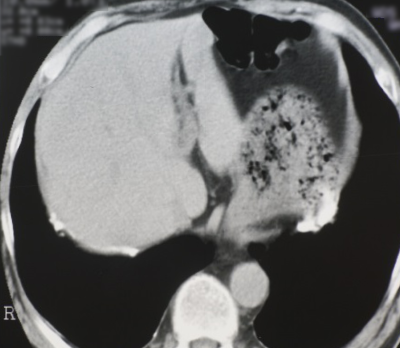

700床を超す著明な国立A病院で肺がんの治療を十分に受けていた建設大工さんの胸部CT写真が写真1です。明らかな胸膜プラークを認めるのですが、その病院の呼吸器内科医も放射線科医も全く認識していませんでした。そんな中、ご家族がアスベスト(石綿)による可能性を疑い、病院の事務でCD-ROMを借用し、セカンド・オピニオンとして、アスベスト関連疾患の専門医がいる「ひらの亀戸ひまわり診療所」に読影依頼をしました。

ひまわり診療所の医師である名取が診療情報提供書で胸膜プラークをご指摘させて頂き、この患者さんは数か月で労災認定されました。肺がんの治療に優れた病院が、石綿やアスベストとの関連を余り知らない典型例の方です。

写真1 国立A病院 胸膜プラーク